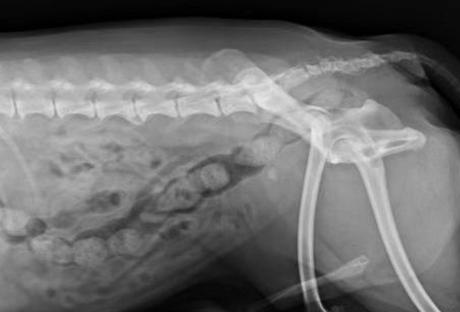

X光检查结果

诊断:X光见膀胱结石,前列腺肿大,B超见前列腺肿大,伴有轻微囊肿

1月后X光检查结果